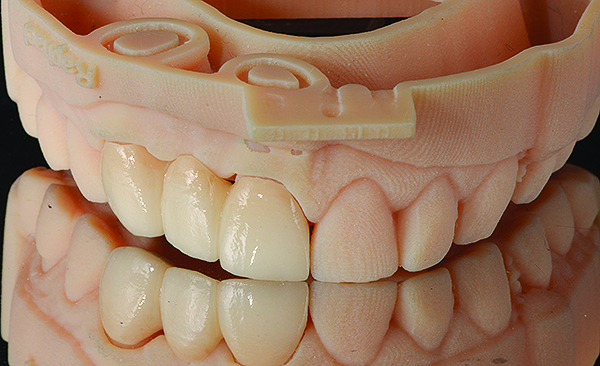

(7.) Completed restoration seated on a model reproduced from the optical impression.

Figure 7